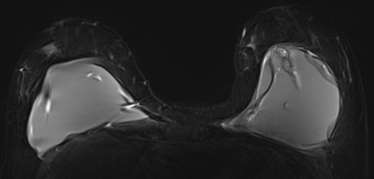

There are few circumstances where MRI is used as an adjunct to diagnose equivocal (uncertain) findings on mammography, sonography or physical examination. The first indication is a patient with persistent bloody or cytologically abnormal nipple discharge. MRI may also be useful for a suspicious finding seen only on one mammographic view that is not amenable to conventional biopsy. Breast MRI is also indicated in the evaluation of clinically suspected silicone implant abnormality or rupture. Due to its high spatial resolution and the contrast between implants and soft tissues, it has the highest sensitivity and specificity for implant rupture among imaging modalities and can be used to assess associated complications involving the surrounding breast tissue, chest wall and axilla7. Lastly, it can be used to evaluate patients with unclear but persistent physical examination findings that are mammographically and sonographically occult5.